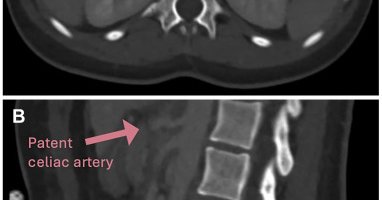

šŸŽÆCeliac artery occlusion from Median Arcuate Ligament Syndrome treated with ligament release alone. No bypass. No complex revascularization. Post-op CTA at 5 weeks shows sustained patency + complete symptom relief. šŸ‘‰ https://t.co/reC69RJmsx #MALS #VascularCompression

We present the case of an 18-year-old female diagnosed with Median Arcuate Ligament Syndrome (MALS) who presented with celiac artery (CA) occlusion. An open surgical approach was employed, the median...